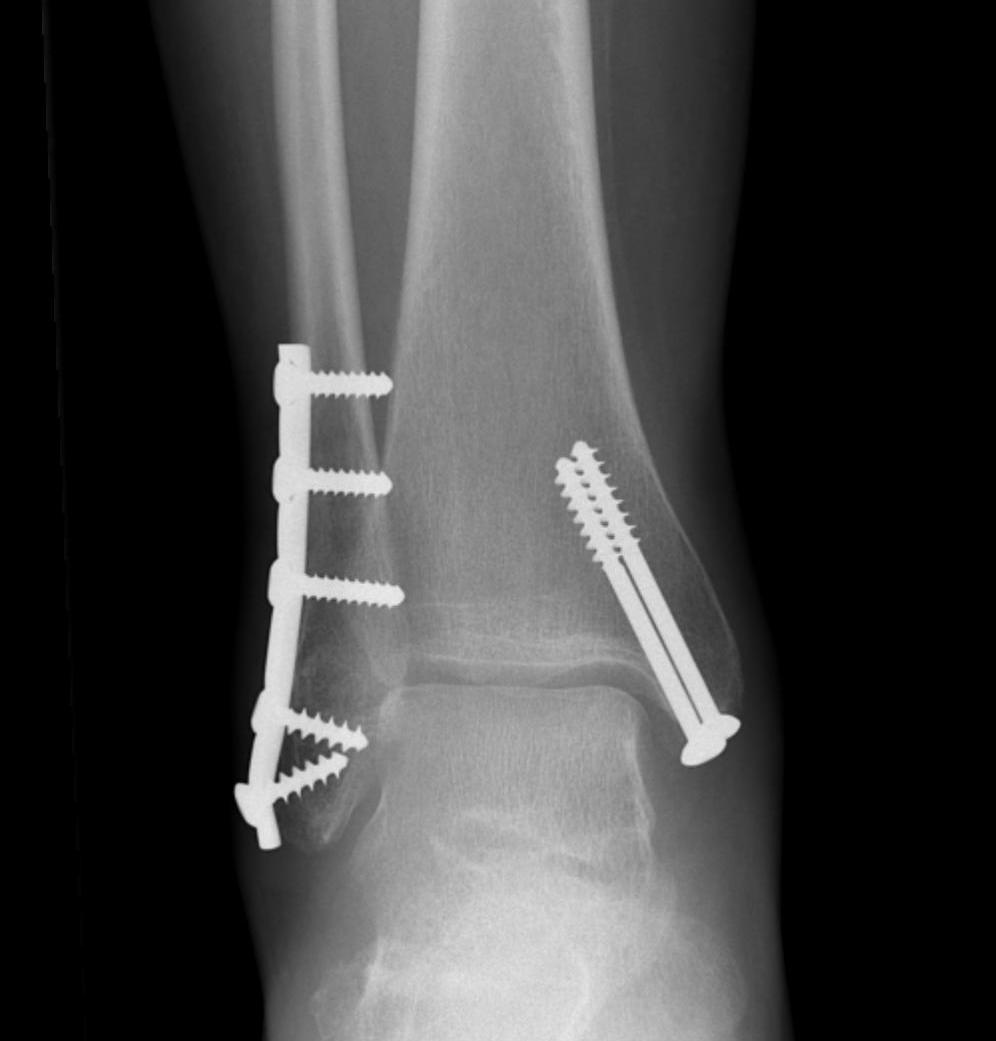

Many fractures can be treated without surgery, if the fractures are in place anatomically and can be maintained in this position with a cast. When there is significant displacement, or indications that there is significant ligament injury, surgery is recommended.

The main risk of the surgery is infection. This risk is low, about 1/100. Reducing swelling after surgery is critical, so keeping it up in the air when sitting or lying is very important. There can be some numbness around the incision, and there is a small risk of deep vein thrombosis. Usually there must be a period of non weight bearing for six weeks while the injury heals; however, early range of motion is useful to prevent or minimize stiffness. It can take 6 – 12 months to fully recover from these injuries.